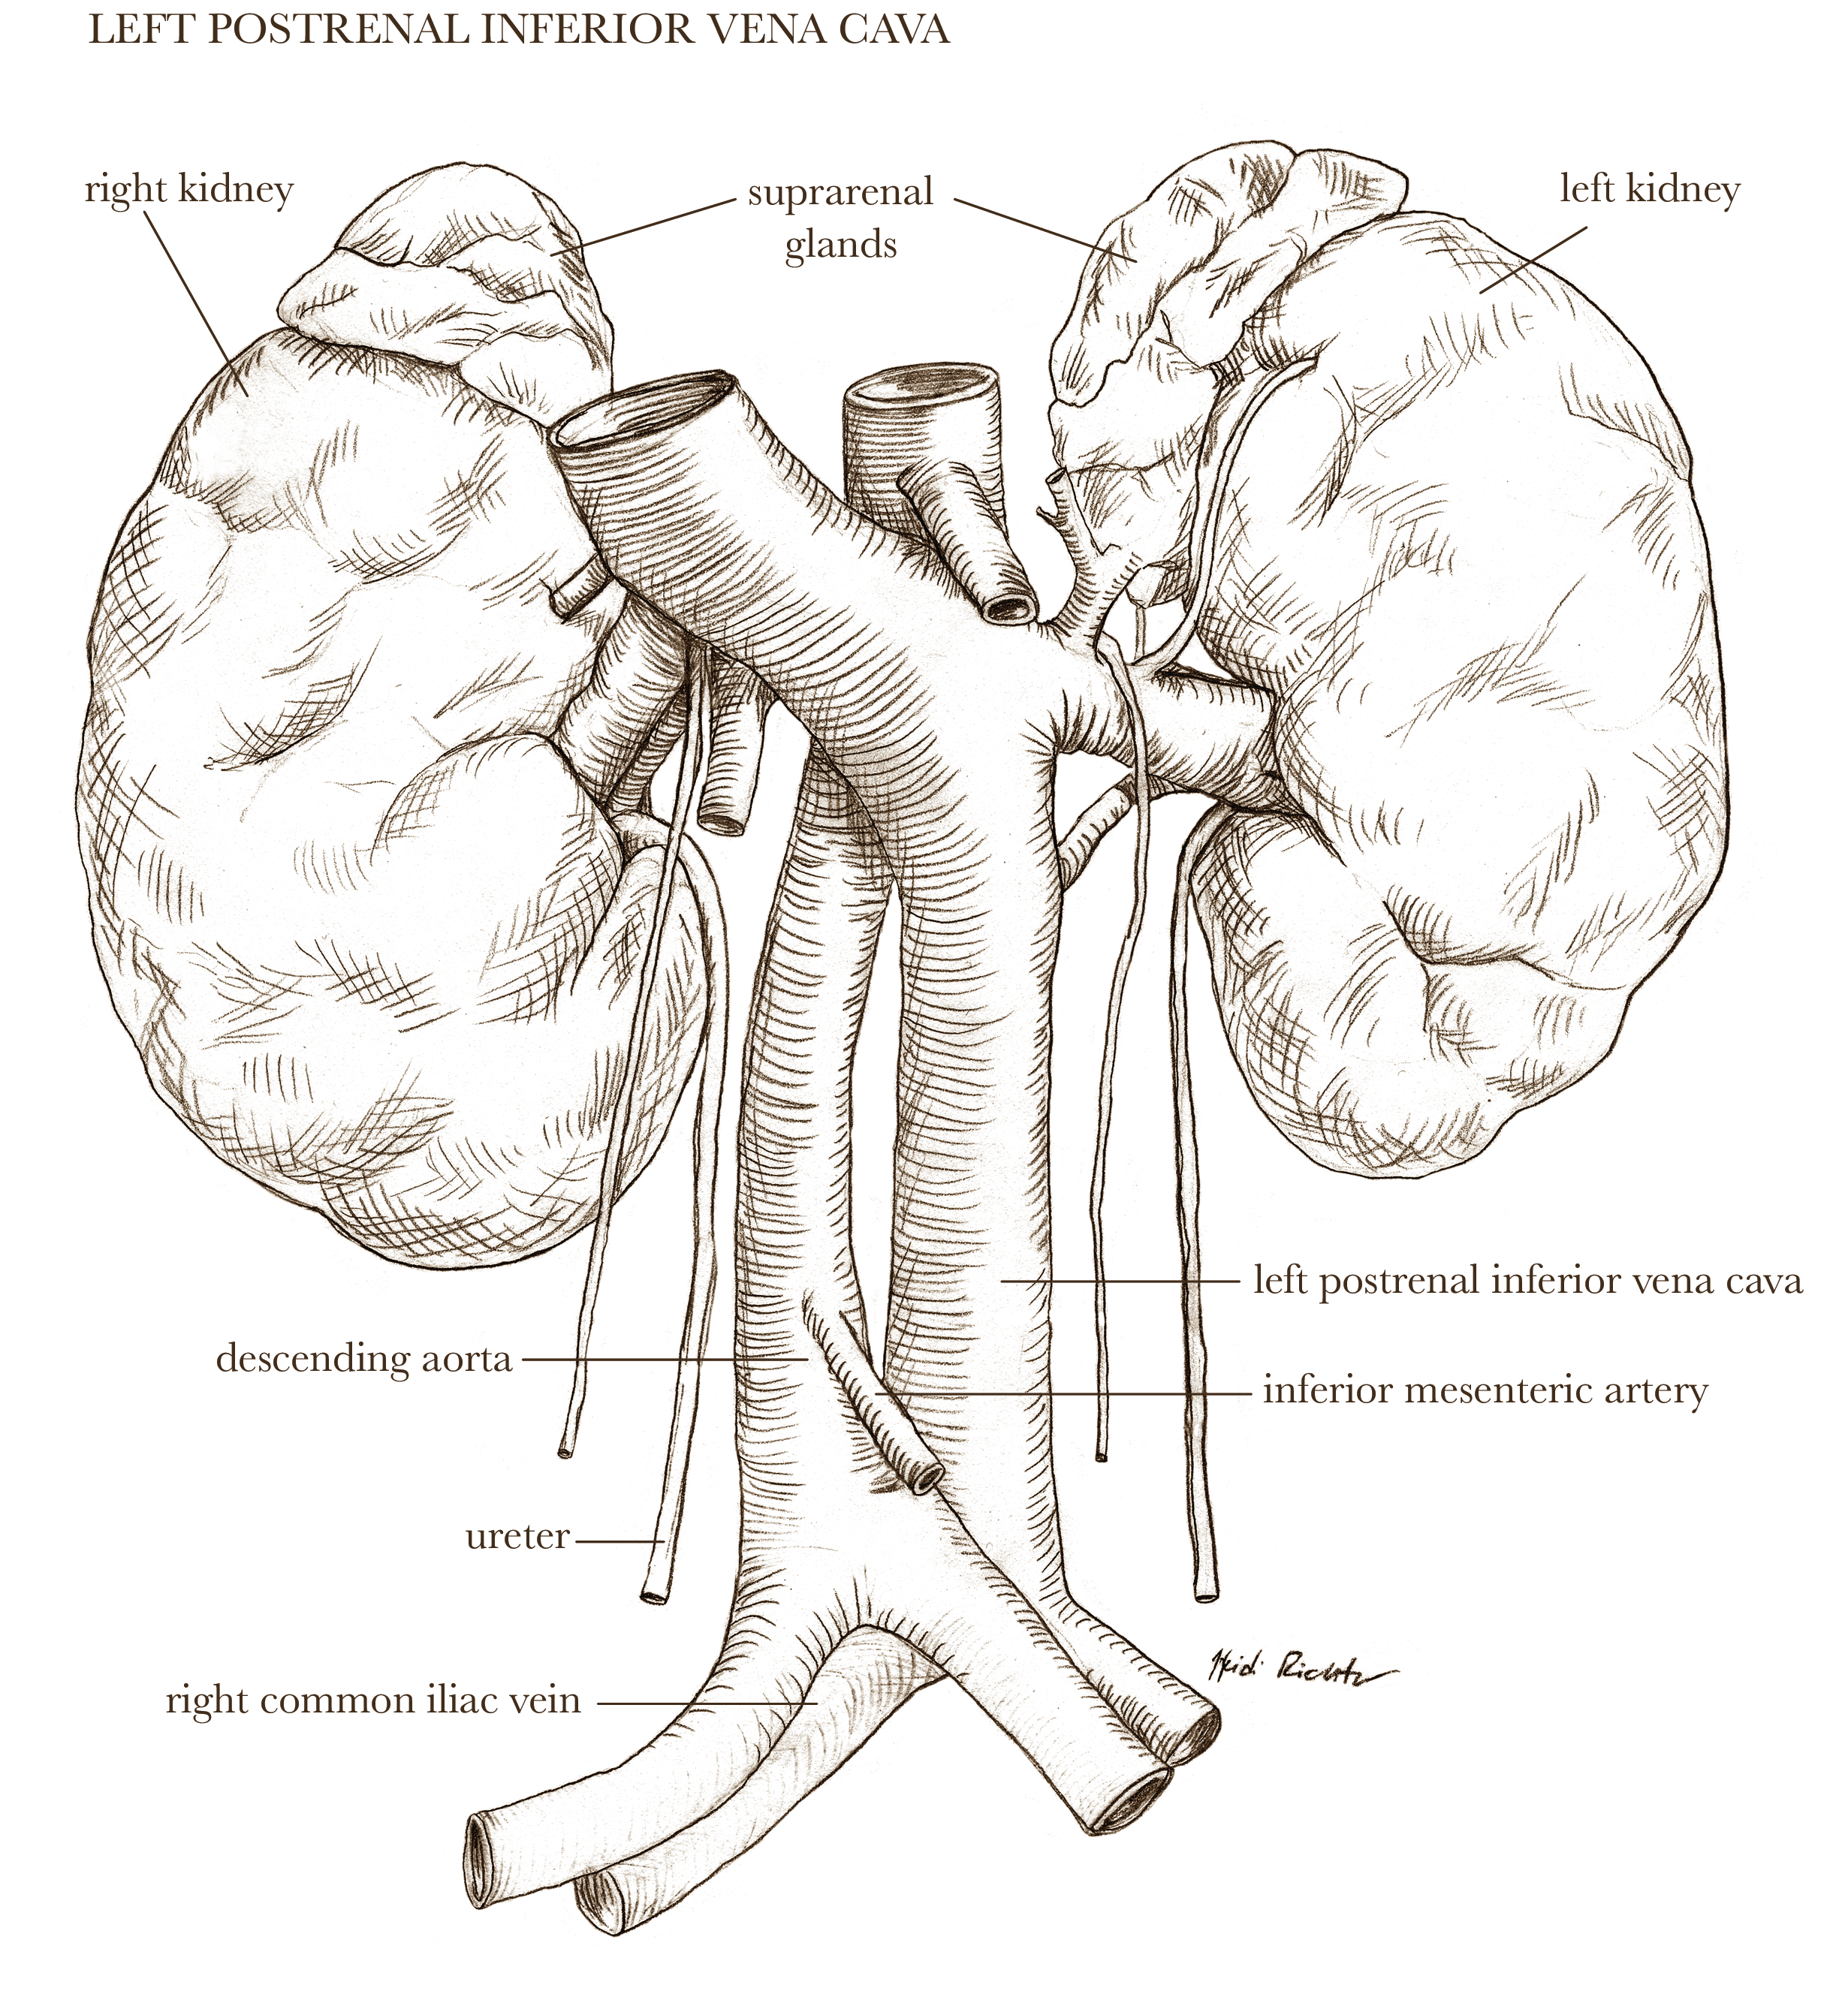

Textbook illustration

I have nearly twenty years of experience in text book publishing, having illustrated books from grade school to graduate level, and in subject areas from human anatomy to biology and geology. I never say no to projects involving dinosaurs.

Medical-legal illustration

I can create client-specific illustrations for your personal injury or malpractice cases to both inform the jury (who often don’t have experience with hospital images) as well as gain sympathy for the affected individual. I can work directly with medical experts to ensure accuracy and admissibility in court.

Illustrations shown below are owned by the artist and available for non-exclusive licenses, contact me for more information.